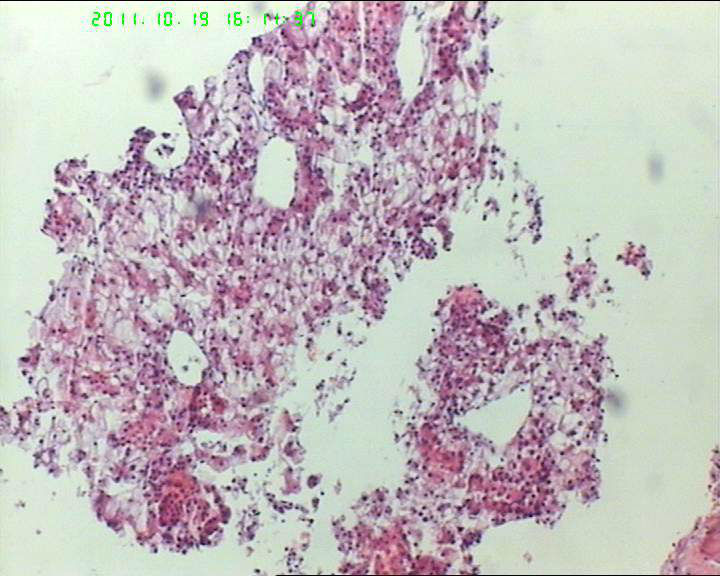

71岁男性肝脏占位,ct示低密灶,大三阳,afp高,转氨酶略高。该诊断什么呢?

• 71岁男性肝脏占位,ct示低密灶,大三阳,afp高,转氨酶略高。该诊断什么呢?图1